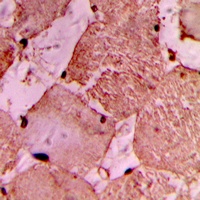

MYLIP antibody (Center) immunohistochemistry analysis in formalin fixed and paraffin embedded human brain tissue followed by peroxidase conjugation of the secondary antibody and DAB staining. This data demonstrates the use of the MYLIP antibody (Center) for immunohistochemistry. Clinical relevance has not been evaluated.